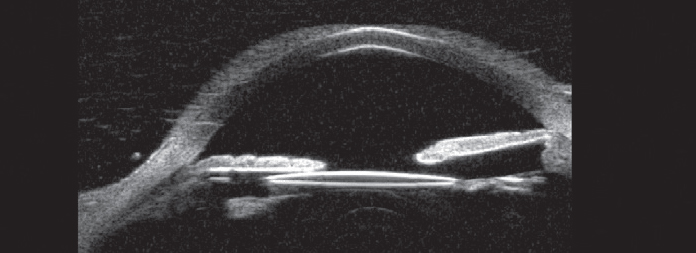

![]() |

| Figure 3. Ultrasound biomicroscopy shows dislocation of a portion of the intraocular lens out of the capsular bag with a point of contact between the lens optic and the posterior iris. (Courtesy Karishma Chandra) |

The patient continued to have recurrent symptoms. She presented three months later with elevated IOP, corneal edema, iritis and vitreous hemorrhage. An anterior segment exam showed temporal dislocation of a one-piece IOL out of the bag into the sulcus. Ultrasound biomicroscopy confirmed chafing of the intraocular lens in the sulcus and the posterior iris (Figure 3). The patient underwent pars plana vitrectomy and IOL exchange with a three-piece intraocular lens in the sulcus and subsequent resolution of symptoms.